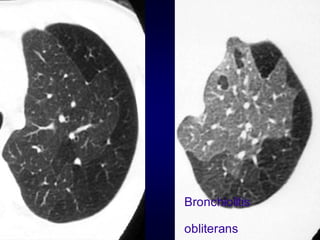

Airtrapping: Airway

Disease

Bronchiolitis obliterans (constrictive bronchiolitis)

idiopathic, connective tissue diseases, drug reaction,

after transplantation, after infection

Hypersensitivity pneumonitis

granulomatous inflammation of bronchiolar wall

Sarcoidosis

Asthma / Bronchiectasis / Airway diseases

Airway Disease

what you see……

In inspiration

sharply demarcated areas of seemingly increased

density (normal) and decreased density

demarcation by interlobular septa

In expiration

„black‟ areas remain in volume and density

„white‟ areas decrease in volume and increase in

density

INCREASE IN CONTRAST

DIFFERENCES

AIRTRAPPING

Bronchiolitis

obliterans